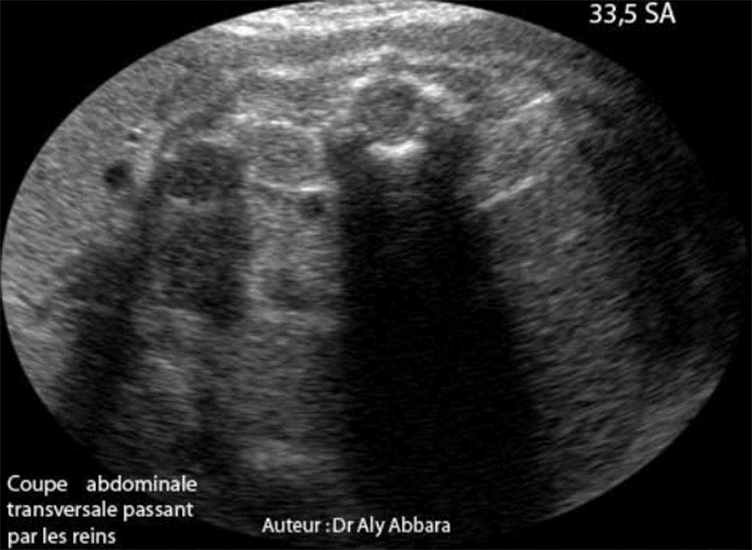

Hypoplasie rénale bilatérale sévère à 33,5 SA - coupes rénales transverses

Hypoplasie rénale fœtale bilatérale et sévère découverte à 33,5 SA

Coupes échographiques transversales des reins fœtaux hypoplasiques avec des images

échographiques permettant de les comparer aux reins normaux.

• Il s'agit d'une hypoplasie rénale fœtale bilatérale et sévère découverte fortuitement à 33,5 SA lors d'une exploration échographique dans le cadre du bilan systématique pour légère menace d'accouchement prématuré.

• L'échographie met en évidence la présence d'un anamnios avec deux petits reins hyper-échogènes :

• Rein gauche : 12 x 15 x 29 mm de diamètres avec volume évalué à (2,7 cm3) ce qui est largement inférieur au 3e percentile.

• Rein droit : 12 x 14 x 28 mm de diamètres avec volume évalué à (2,4 cm3) ce qui est largement inférieur au 3e percentile.